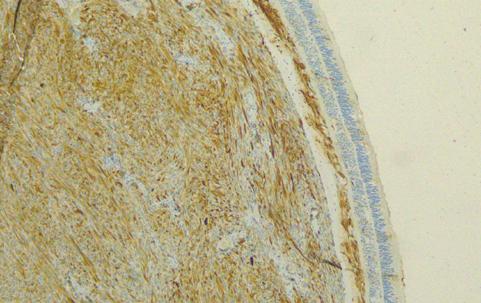

Estudio inmunohistoquímico: Se realizó con anticuerpos monoclonales en un procesador automático de tejidos Benchmark GX. En la detección se utilizó el sistema supersensitivo de Biotina-Estreptavidina, y en la visualización el cromógeno Diaminobencidina (DAB).

RESULTADOS:

Actina: Negativo. Desmina: Negativo; Ki 67:15%.

Los hallazgos inmunohistoquímicos y de hematoxilina eosina en correlación con los antecedentes de la paciente indican diagnóstico de melanoma de origen ocular primario. Por lo tanto, se solicita interconsulta con Oncología que requiere nuevos estudios complementarios y continúa atendiendo a la paciente.